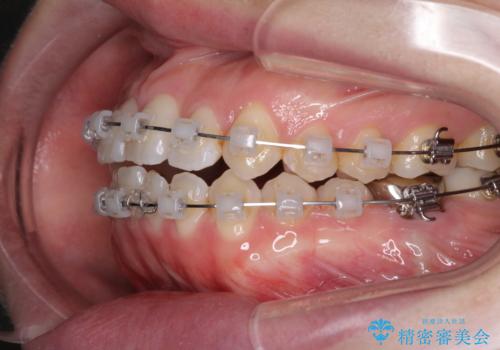

前歯のデコボコを治したい ワイヤー矯正

- クリアブラケット

- 前歯のデコボコが気になるとのことで来院された患者様です。

目立たない装置と金属のワイヤーで矯正治療を行うこととしました。

1年半程度の期間を見込んでいましたが、上下の真ん中の位置をできる限り合わせるための調整に少し時間がかかってしまいました。

咬み合わせが安定し、前歯の汚れも付きにくくなりました。